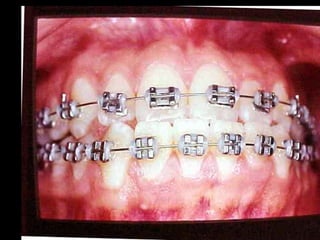

La paciente fuemanejada iatrogénicamente por 5 años Utilizando diferentes implementos ortodóncicos La regla es clara: Laterognatias de más de 2º son quirúrgicas

Eliminación de rotaciones. Correcciónde las discrepancias de longitud de arco. Posición de los incisivos y molares por medio del torque adecuado. Llevar cualquier otra alineación en el arco. Eliminación de rotaciones. Corrección de las discrepancias de longitud de arco. Posición de los incisivos y molares por medio del torque adecuado. Llevar cualquier otra alineación en el arco.

Evita el potencialde recidiva Aumenta la velocidad y eficacia del tratamiento